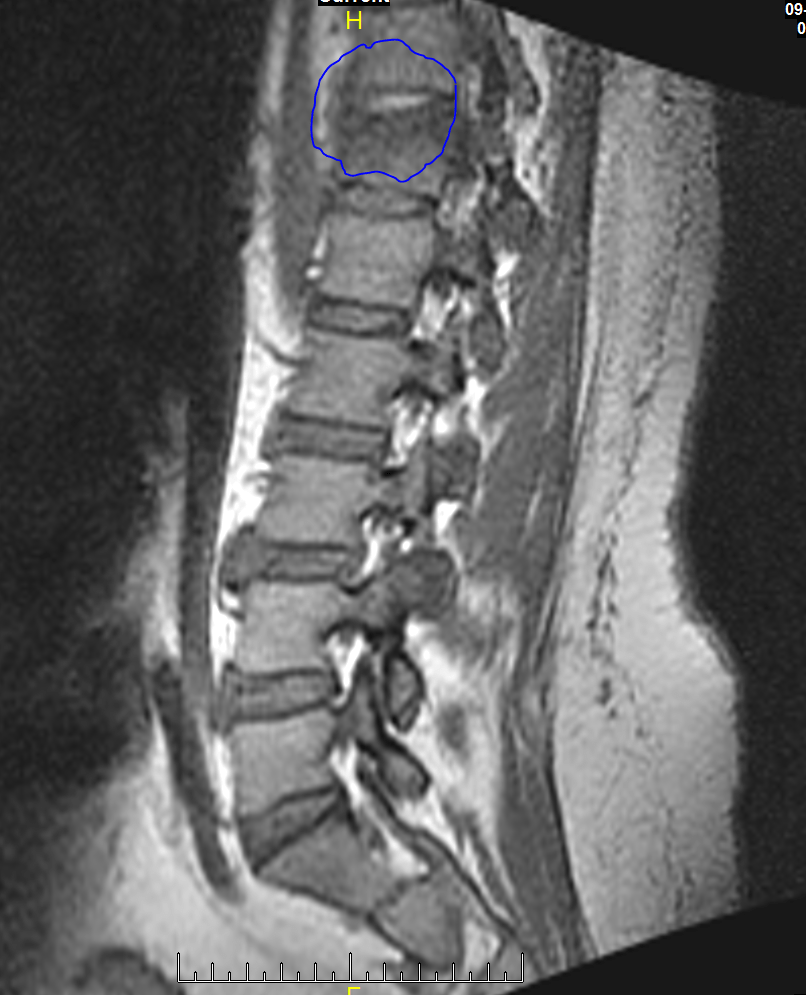

The prevertibral soft tissue are normal in appearance. THere is marrow edema in the T12 vertibral body, and there is a slight depression of the superior endplate. This is consistent with an acute to subacute compression fracture. The posterior wall of the vertebral body is intact. The disks above and below this vertibral body appear normal.

1. There is compression fracture of T12 without involvement of the posterior wall. The anterior wall is depressed approximately 25%.

Here is an MRI picture of the spine. You are look at it from a side view. I circled the fractured area.